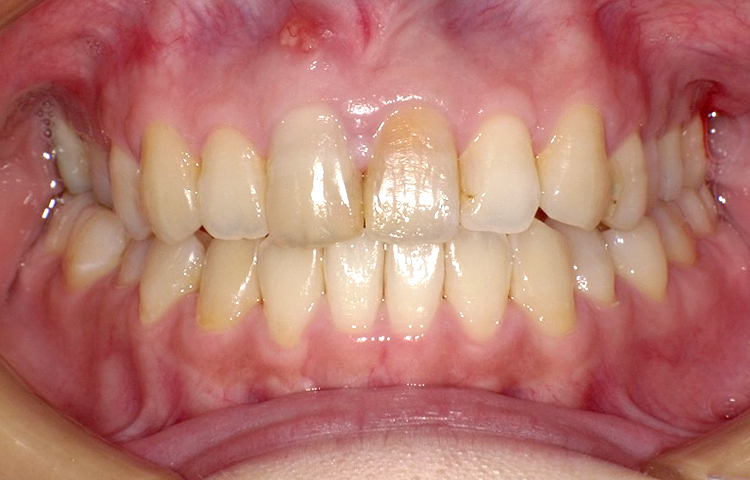

症例4

治療前

治療後

| 主訴 | 右上1番出ている 上のみ部分矯正希望 |

|---|---|

| 治療 期間 |

約8ヶ月 |

| 治療費 | 220,000円(税込)/調整費用別途 |

| 治療 内容 |

上の前歯部にワイヤーを着けて進めていく、プチ矯正で施術。 |

| 治療の リスク |

奥歯を動かさないので、前に出して並べていく。 歯と歯が移動するスペースを作るので、知覚過敏の症状がまれにでる。 装置による清掃の難しさから、歯肉炎や歯周病、虫歯の進行がするリスクが高まる。 歯を動かすことで、歯茎が下がるリスクある。 矯正終了後は、リテーナーを使用し、後戻りを防ぐ必要がある。 |